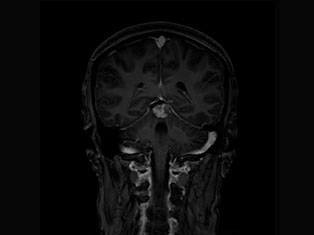

Brain Tumors

A brain tumor is a mass or growth of abnormal cells in your brain. Many different types of brain tumors exist. Some brain tumors are noncancerous (benign), and some brain tumors are cancerous (malignant).